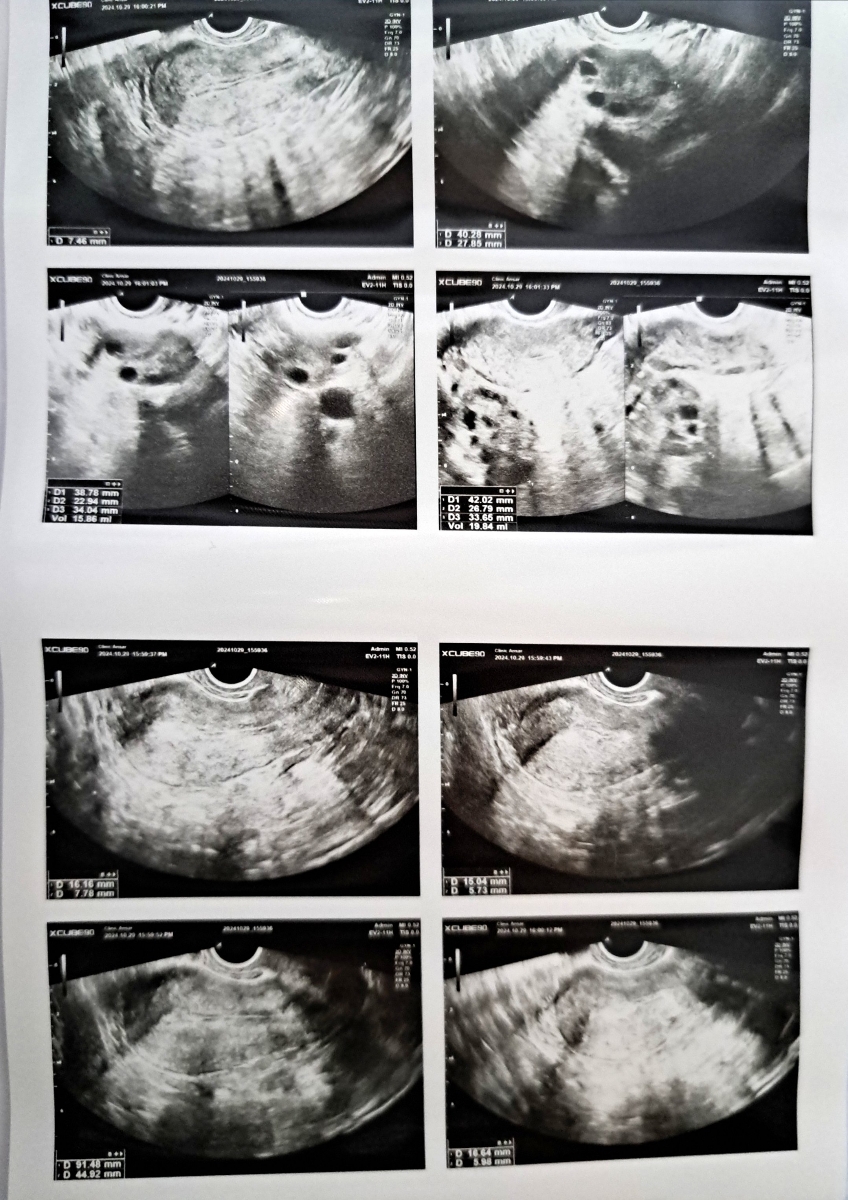

سونو واژینال

ولی درمورد سونوگرافی لگن شیرین جانم بارداری قبلیت راحت اتفاق افتاد ؟ چون بنظر اندومتریوز داری که البته خطرناک نیست فقط گاها چالش سرراه باردار شدن هست

راستش قبل از بارداریم هم مثل الان همچین مشکلی برام پیش اومد یعنی لکه بینی بین پریود و نامنظمی سیکل هام. سونو انجام دادم گفت پولیپ دارم و تنبلی تخمدان. داروهایی که دکتر بهم داد قرص دوفاستون و روکین بود.

حدودا دو ماه دارو استفاده کردم و پیاده روی منظم داشتم ده کیلو وزنم کم شد. پریودم منظم شد و من فکر میکردم هنوز تنبلی تخمدان دارم و قرص روکین هم میخوردم جلوگیری دیگه ای نداشتم ولی متوجه شدم باردار شدم.

خانم دکتر من سونوگرافی که بعد از اون درمان قبلی انجام دادم رو دارم. برای خرداد سال ۹۹ هست که باز گزارش pco داده و من ماه بعدش متوجه شدم باردارم.

عزبزم الان هک تنبلی تخمدان طبق صحبت های قبلیمون مشهوده بنظر من همون روال گذشته رو جلو برو البته دوفاستون نمیخواد روکین بخور، ولی 3 ماه دیگه سونوگرافی پیگیری بده و. اگه زمانی قصد بارداری داشتی حتما عکس رنگی از رحم هم انجام بده مطمئن بشیم بخاطر اندومتریوز چسبندگی نداری